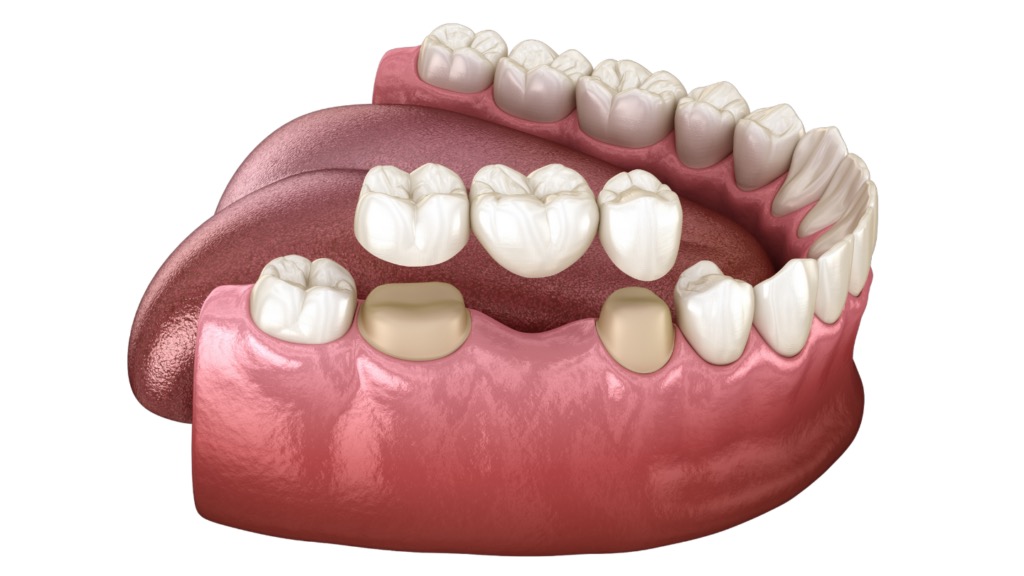

✅ 3. 做牙冠(假牙)時齒質高度不足、或不符合假牙製備原則

假牙要牢固,需要一定的齒質高度做「抓握」結構;不夠就容易鬆脫。

5. 🔸 傷口癒合後再進行補牙或製作假牙

👉 讓補牙、假牙更密合、不易再蛀

👉 提升保存牙齒的成功率